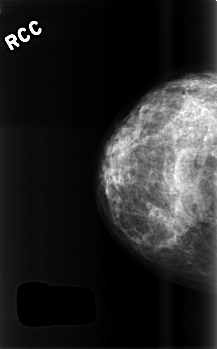

C_0509_1.RIGHT_CC

RIGHT_CC LINES 4528 PIXELS_PER_LINE 2816 BITS_PER_PIXEL 12 RESOLUTION 50 NON_OVERLAY